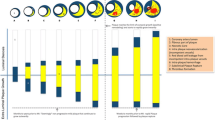

Arterial remodeling of individual plaques seems to be very dynamic over time, according to experimental data from animal studies. A considerable percentage (∼75 %) of ostensibly high-risk TCFAs in human arteries may heal and become quiescent during the natural course of atherosclerosis, possibly because of arterial remodeling that may reduce the local pro-inflammatory low endothelial shear stress (ESS) environment, underscoring the complexity of pathophysiologic mechanisms leading to clinical events (Fig. 1) [5••, 26••, 27]. Furthermore, it has recently become clear that the phenotypic manifestations of atherosclerosis are not uniform even along the length of an individual plaque, but are very heterogeneous with a variety of plaque morphologies, remodeling characteristics, and local hemodynamic environments along their length, and the longer the plaque length the more heterogeneous the various plaque characteristics along that plaque (Fig. 2) [28].

Dynamic natural history of local plaque characteristics in individual porcine coronary plaques. Intravascular ultrasound-based 3D artery reconstruction was serially performed at 5 consecutive time points in vivo in 5 diabetic, hypercholesterolemic pigs. ESS and vascular remodeling were assessed along the course of each of the 3 coronary arteries. a Local arterial remodeling characteristics. A dynamic and heterogeneous progress in arterial remodeling of individual lesions was noted over time. The majority of segments with compensatory remodeling remained with that remodeling pattern over time. Only a small minority of segments with either excessive expansive or constrictive remodeling at week 4 continued to exhibit the same remodeling pattern throughout their evolution (adapted from Reference [26••], with permission). b Local ESS characteristics. Local ESS in individual segments (n = 184) frequently changed from low ESS (<1.2 Pa; lower row) to higher ESS (intermediate/high, ≥1.2 Pa; upper row) between consecutive time points. The black portion of the pie charts at each time point represents the proportion of segments with low ESS at the immediately preceding time point; the white portion represents the proportion of segments with higher ESS at the preceding time point (reprinted from Reference [27], with permission)

Heterogeneity of local plaque characteristics within individual human plaques. Coronary angiography and IVUS-derived 3D artery reconstruction was performed in 219 patients of the PREDICTION study, and 371 plaques were identified (adapted from Reference [28], with permission). a Arterial remodeling patterns per plaque. The number of arterial remodeling patterns in an individual plaque progressively increased as the plaque became longer. b. ESS patterns per plaque. The number of ESS patterns in an individual plaque progressively increased as the plaque became longer